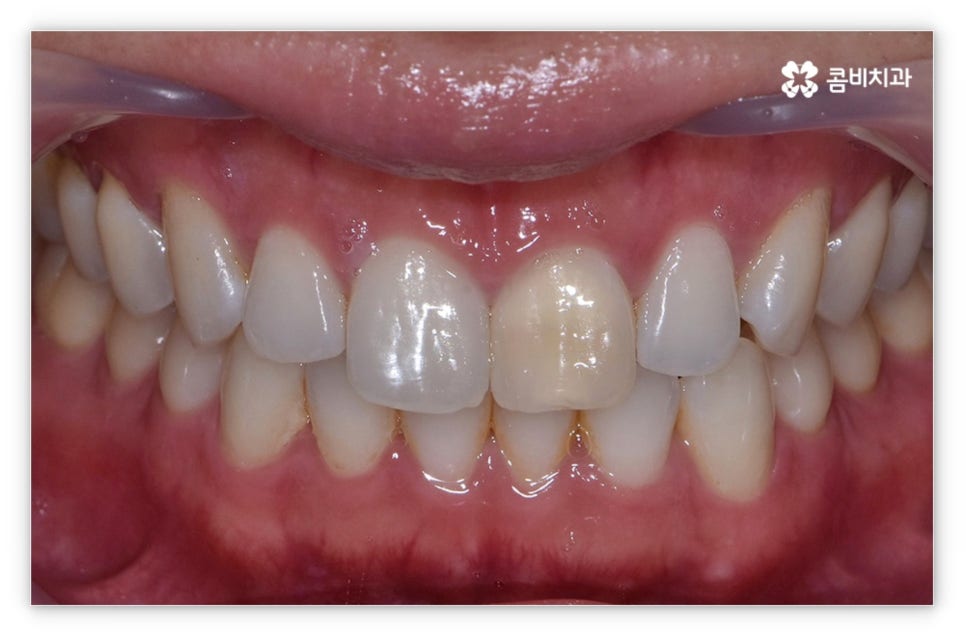

살펴본 바와 같이 앞니설측교정 의 장점에도 불구하고 아랫니 부분은 장치가 혀에 닿게 되기 때문에 환자분들께서 불편함을 느낄 수 있고 혹시라도 혀가 브라켓에 잘못 쓸리거나 눌렸을 때 통증이 발생할 수도 있으며 발음이 불분명해지는 문제가 생길 수 있는데요. 이러한 이유로 앞니설측교정 에 대해서 고민이 되시는 분들은 윗니 부분은 설측으로, 아랫니 부분은 일반 교정처럼 순측으로 진행하는 콤비 교정에 대해서 알아보시면 좋을 거예요. 위의 사진에서 살펴보실 수 있는 경우가 바로 이렇게 콤비 교정으로 진행한 환자분의 케이스인데 아랫니의 경우 보통 입술에 가려 별로 드러나지 않는 데다가 치아 색상인 세라믹 재질로 된 브라켓을 이용하기 때문에 설측 교정과 비교해도 심미성이 크게 떨어지지 않는다는 것을 알 수 있어요. 콤비 교정의 경우 설측 교정보다 비용적인 부담도 줄일 수 있으니 각 장치에 대한 장단점을 의료진분들과 충분히 상담하셔서 자신에게 맞는 장치를 선택하시면 좋을 거예요.